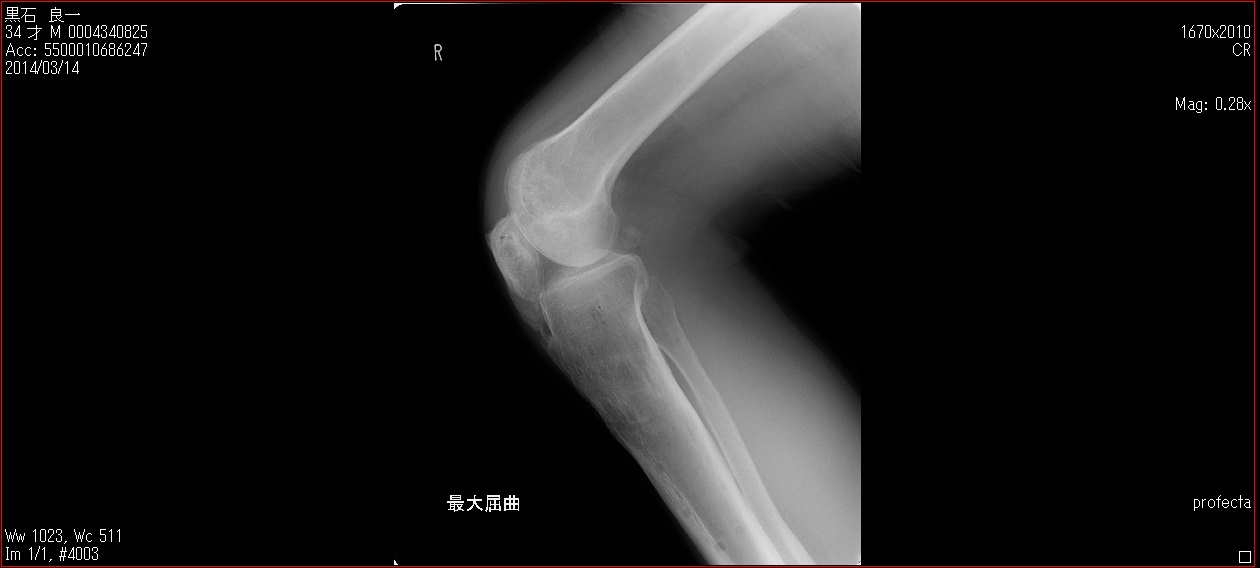

[Ortho] patella baja

Пациент 27 лет приехал для удлинения роста по эстетическим показаниям. Метод: крослатеральное двухэтапное удлинение голеней 4см и бедер 3 см.  Между этапами удлинения уезжал к себе домой в Японию на реабилитацию. Между этапами удлинения движения в коленных суставах разгибание полное сгибание 90-85. После выписки (февраль 2012) даны соответствующие указание постепенно возрастающей нагрузки и ЛФК коленных суставов.

В настоящий момент жалобы на ограничение сгибания в коленных суставах. Снимки прилагаются.

Вопрос: почему возникло такое осложнение? Поверьте приходилось удлинять намного больше, а тут всего на 3-4 см и такое осложнение на обеих конечностях у одного пациента?

Что можно сделать? У кого есть опыт лечения patella baja?